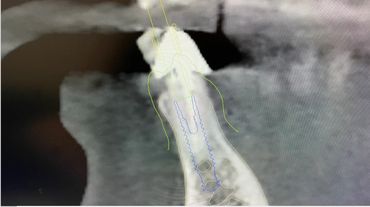

Unique connection because of small diameter.

Where and how to use 2.9 Narrow implant